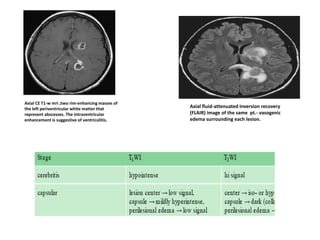

Axial CE T1-w mri ;two rim-enhancing masses of

the left periventricular white matter that

represent abscesses. The intraventricular

enhancement is suggestive of ventriculitis.

Axial fluid-attenuated inversion recovery

(FLAIR) image of the same pt.- vasogenic

edema surrounding each lesion.